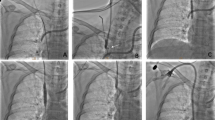

IVC recanalization was performed via right femoral venous access, and then the right jugular vein was cannulated if the femoral venous access failed. A 5F pigtail catheter was introduced into the IVC for venography. A 0.035-inch guide wire and a 5F headhunter catheter (Cook, Bloomington, IN, USA) were introduced to the IVC for recanalization. If this failed, the rigid end of the guide wire or J-type blunt needle was introduced into the distal part of IVC lesion for sharp recanalization. After withdrawing the guide wire, a 0.035-inch stiff guide wire of 260 cm in length (Amplatz Super Stiff; Boston Scientific, Massachusetts, USA) was introduced into the IVC. A 14F long sheath and gooseneck capture were introduced, and the guide wire was pulled out to establish a JFV route. Predilation was performed via long sheath or small diameter balloon catheter10,12. A large diameter balloon catheter (Cook) was inserted for IVC angioplasty via the stiff guide wire (Fig. 1).

JFV route establishment and IVC recanalization. (a) A segmental occlusion was shown in the suprahepatic IVC by venography via femoral access. (b) Downward recanalization was performed via jugular access after transfemoral access failed. (c) A 0.035-inch stiff guide wire was introduced into the distal IVC, and a gooseneck capture was introduced to pull out the guide wire. (d) Venography was performed via a 14 F long sheath after JFV route establishment. (e) Angioplasty was performed using a large balloon (30 mm diameter). (f) Venography confirmed successful recanalization and widely patent IVC without bleeding.